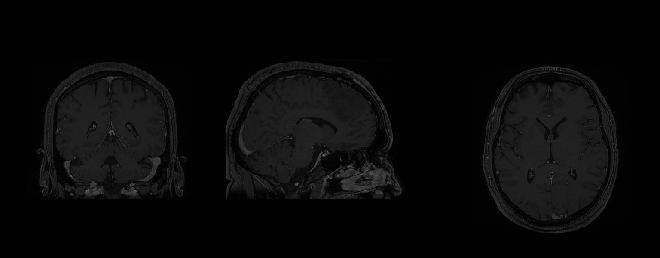

Brain tumors are such abnormal growths found within the human cranium. Given the complex and sensitive nature of the brain, a non-invasive technology, i.e. Magnetic Resonance Imaging (MRI), is the most popular pick for brain tumor diagnosis. These images are three-dimensional scans of a patients brain and can be visualized on either of its three respecting image planes (Coronal, Sagittal and Transversal), as shown in Figure. 1 [9]. Each perspective plane displays its information regarding a potential abnormal growth within the cranium. This classification of MRI scans based on the perspective planes has been noted to improve the analytical results while detecting brain tumors [10].

Refer to caption

Figure 1: The three perspective planes used in medical imaging are Axial (or Transversal), Coronal and Saggital [9].